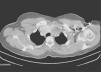

Benign metastasizing leiomyomatosis of the lung